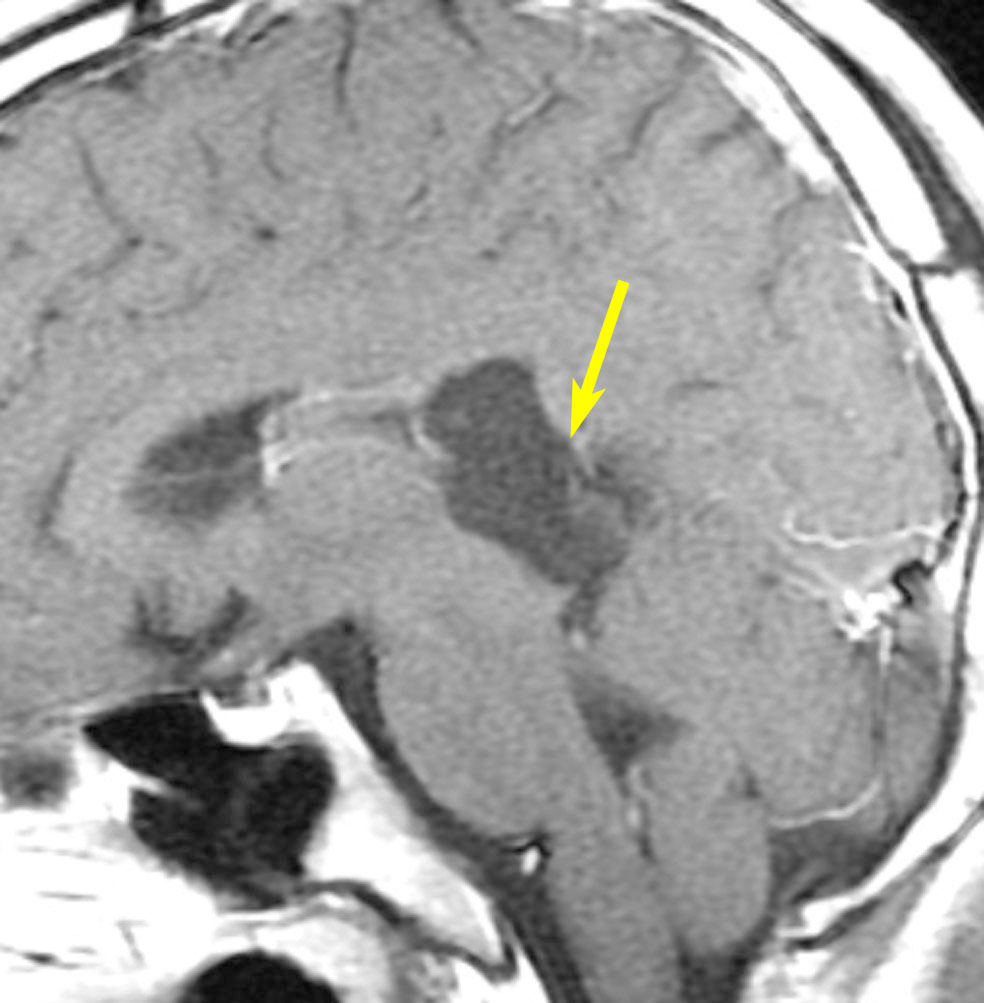

脳幹部に食い込んでいる類表皮のう胞をどうするか

とても若い患者さんで歩行障害などの脳幹部症状は全くありませんでした。第4脳室に発生して脳幹部(橋)背側に食い込んでいる類表皮のう胞です。これを全摘出することは難しく,行えば重い脳幹部症状を出す大きなリスクがあります。

患者さんとよくよく相談して,開頭手術で全摘出しました。

薄いのう胞壁を脳幹内部から確実に摘出するためには,橋の背側の脳組織をほじくり回すような手術になります。

術後は体幹失調で術直後は車椅子になりましたが,リハビリで普通に歩行ができるようになりました。眼球運動障害も回復しています。

安易にお勧めできる手術ではありませんでした。